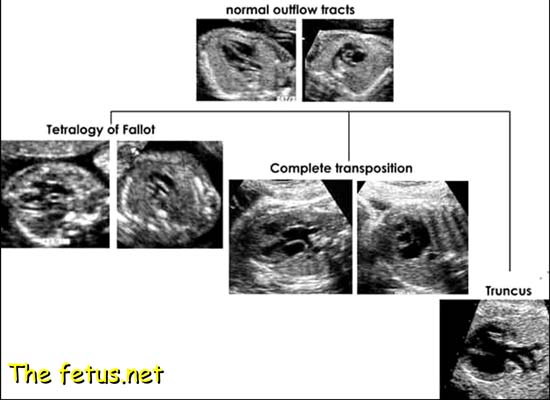

Anomalies de développement des conus sous-aortiques ou sous-pulmonaires ou du tronc artériel, responsables d’une altération des connexions ventriculo-artérielles.

L’incidence des quatre cavités est habituellement normale.

A. Cardiopathies associées à un chevauchement artériel sur le septum inter-ventriculaire

CIV haute sous-artérielle, surplombée par un gros vaisseau qui reçoit simultanément du sang des deux ventricules.

Incidence cinq cavités : Le gros vaisseau chevauche le septum IV et reçoit le sang des deux ventricules.

1.Tétralogie de Fallot

2. Atrésie pulmonaire avec communication interventriculaire (tétralogie de Fallot extrême)

3. Ventricule droit à double issue (VDDI)

4. Tronc artériel commun

Défaut de septation du truncus arteriosus qui donne normalement naissance aux deux gros vaisseaux.

- Un seul gros vaisseau chevauche le septum IV.

- Il bifurque précocement pour donner naissance à la crosse de l’aorte et à l’AP.